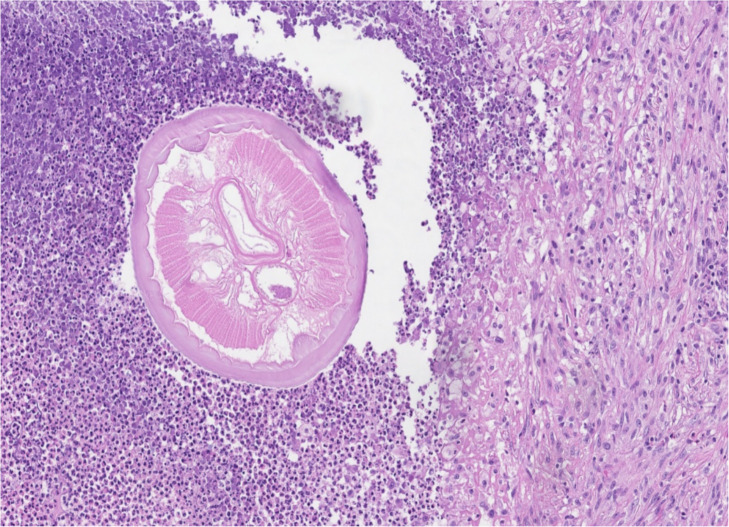

Human dirofilariasis is a rare anthropo-zoonotic disease, mainly detected in Southern and Eastern Europe, Asia Minor, Central Asia, and Sri Lanka. An increasing number of autochthonous Dirofilaria spp. infections has been recently reported in the areas previously considered free of the disease, including northern Europe and the Baltic States. A rare autochthonous case of scrotal dirofilariasis detected in Lithuania was described. Here, a 42-year-old male presented with a 1 cm nodule, limited in the scrotum. A nodule excision was performed. On histological examination, a degenerating roundworm with the features of Dirofilaria spp. (multilayered cuticle, well-developed musculature, focally preserved longitudinal ridges) was detected in the abscess cavity. No additional treatment was needed. Twenty-four publications reporting 28 male genitalia dirofilariasis cases in European countries have been identified.